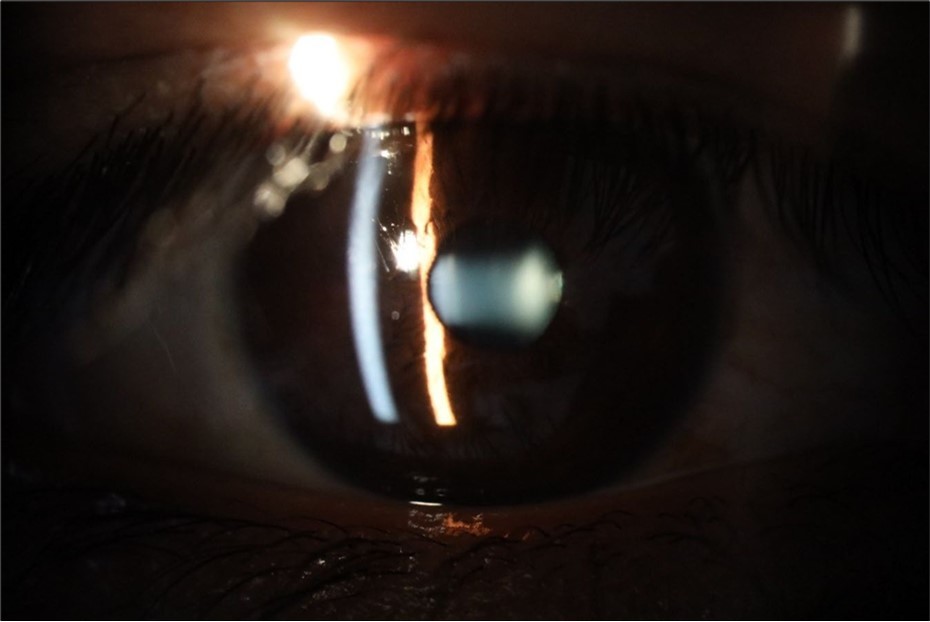

Figure 20.The mirror reflection of the affected (right) eye continues to improve.

Figure 21.The anterior segment of the right eye responds with difficulty to mydriatics, which is usual in diseased eyes.

Figure 23.The mirror reflection of the left eye, without anomalies.

Figure 24.The eye that was not affected by the trauma (left side) remains in good condition.